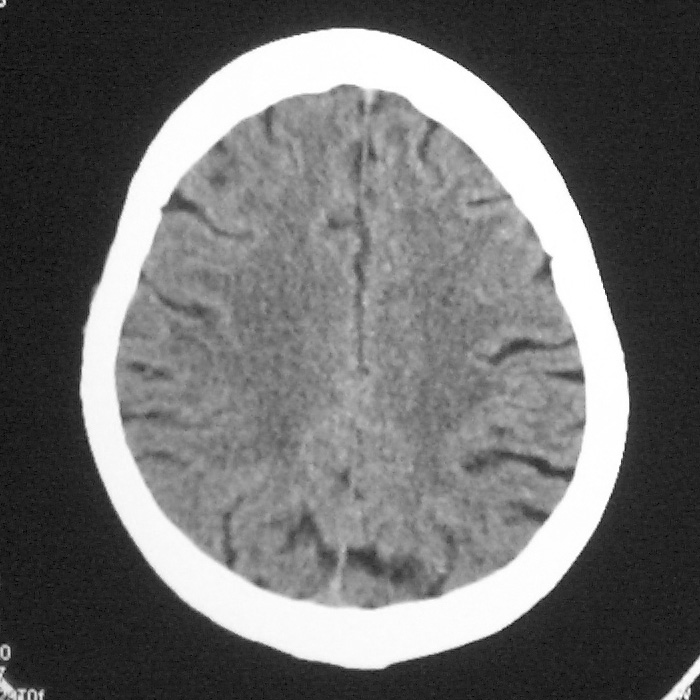

f,70y,口角歪斜、流涎、吐词不清三天

左侧大脑基底节区点状低密度影,边缘清楚,左侧腔梗或软化灶,没什么问题啊?

症状这么明显的话一般不会是单纯面神经麻痹引起的,最好做个mri,如果确实没有问题的话才能考虑面神经麻痹,毕竟这两种病的治疗和预后不一样,这个病人还有脑白质疏松。

左侧半卵圆中心腔梗应当比较明确,右侧基底节好象不明显,不好说,做个mri明确吧

双侧多发腔梗

右侧基底,左侧半卵圆中心腔梗

1、右侧基底,左侧半卵圆中心腔梗。2脑萎缩。

左侧腔隙性梗塞灶,脑萎缩。

左侧基底节区示点状低密度灶,边界清楚,密度均匀,余所示无著变。

意见:腔隙性脑梗塞(左基底节区)

各位老师,报告这么写可以吗?右侧我没有看出来。

左侧半卵圆中心,右侧基底节腔梗。再加个脑萎缩吧

双侧多发腔梗 脑萎缩